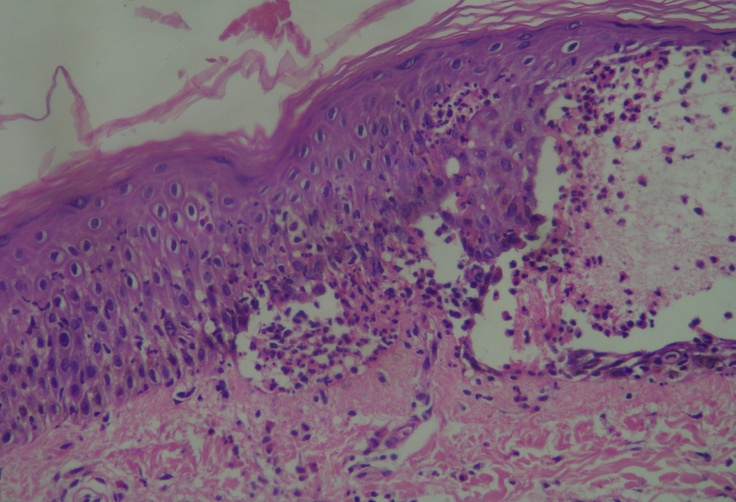

Il pemfigoide bolloso è la malattia bollosa subepidermica autoimmune più comune, che classicamente si presenta con placche eczematose o orticarioidi intensamente pruriginose e bolle tese nei pazienti anziani. La forma lieve o localizzata può essere controllata con corticosteroidi topici, tuttavia le forme più gravi sono spesso difficili da trattare.